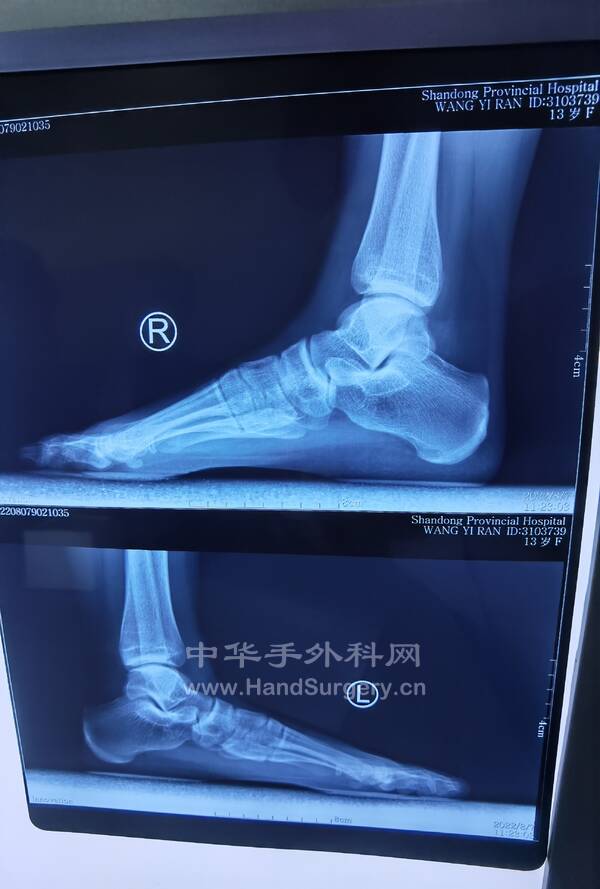

13岁女孩,双足拇外翻,老师建议手术治疗。

IMG_20220807_111810.jpg

IMG_20220807_144920.jpg

IMG_20220807_144949.jpg